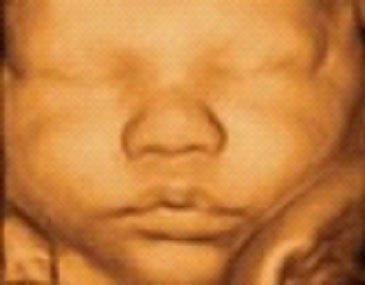

Uc Baby 3d Ultrasound 13798 94a Ave 200 Surrey Bc V3v 1n1 Canada